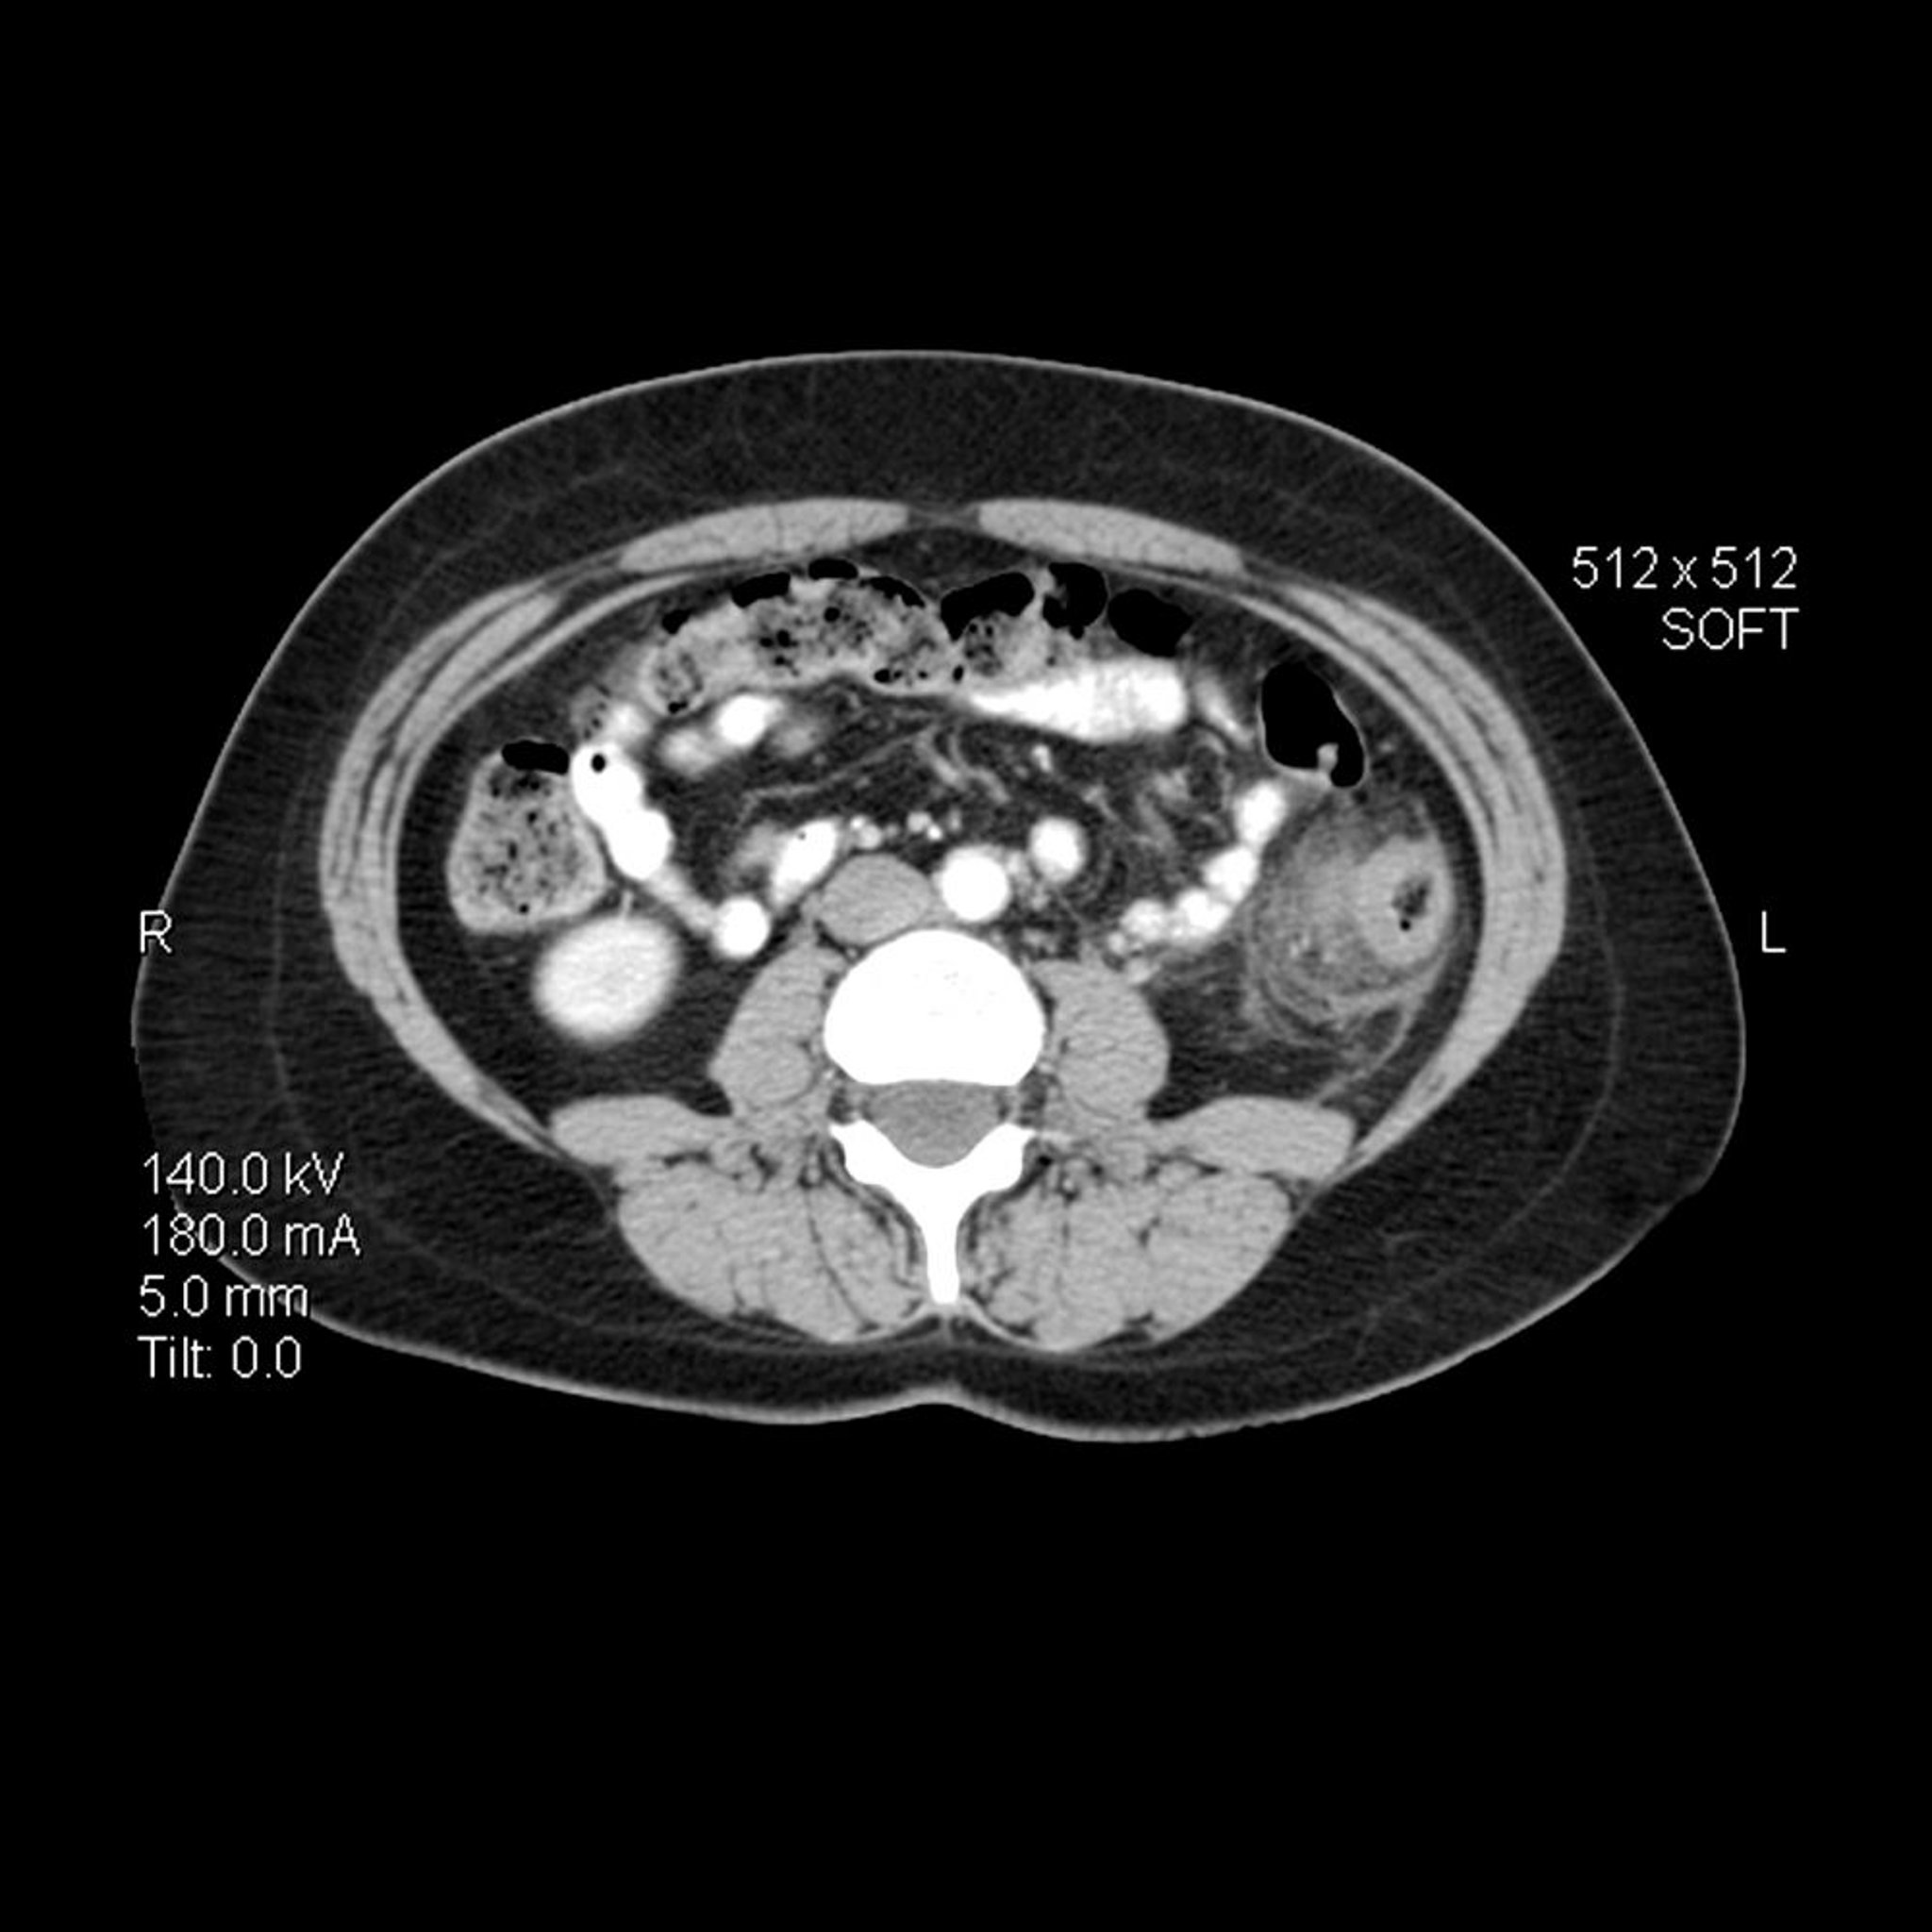

Dans cette image TDM axiale (en coupe transversale) de l'abdomen chez une personne atteinte de diverticulite, la paroi du côlon descendant est épaissie. Il existe également des stries inflammatoires avec une augmentation de la densité de la graisse péricolique adjacente.

LIVING ART ENTERPRISES, LLC/SCIENCE PHOTO LIBRARY